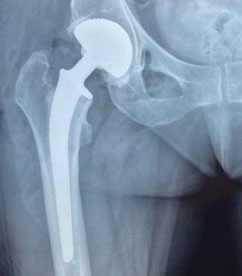

Chirurgie de la hanche

Toutes les pathologies de la hanche sont prises en charge à la Clinique Victor Pauchet à Amiens. La pose de prothèse de hanche par voie antérieure est l'un des domaines d’excellence du service.